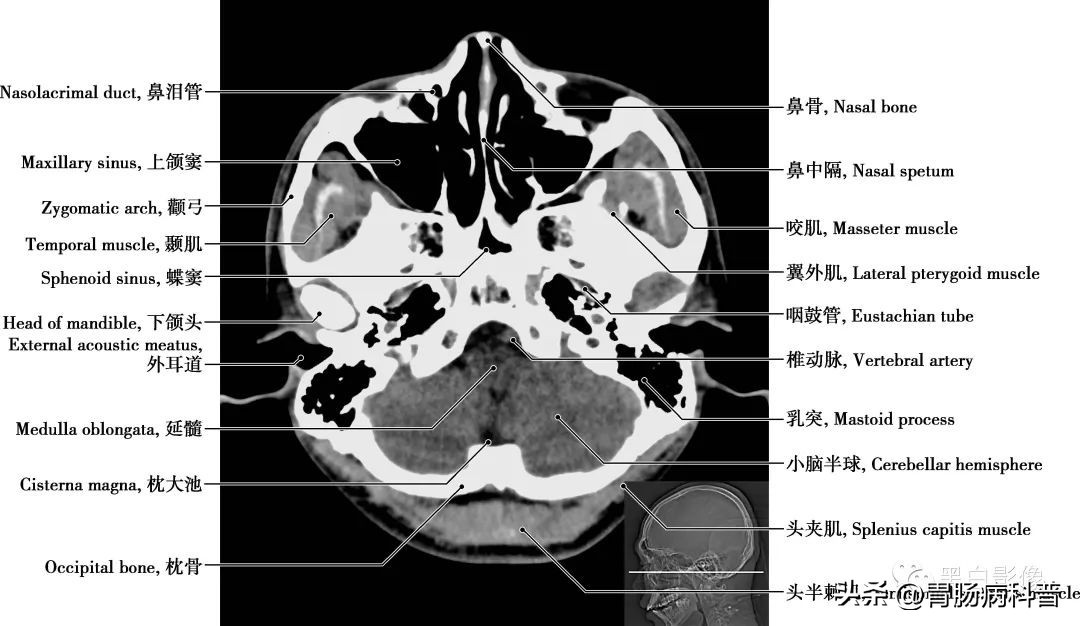

图1-1-18 经下颌头轴位切面

枕大池 又称小脑延髓池,位于颅后窝的后下部,小脑下面、延髓背侧面与枕鳞下部三者之间。向前经小脑溪通第四脑室;向前外经延髓侧面通延髓池。咽鼓管 咽鼓管从鼓室口向内、向前、向下直到咽口,是沟通鼓室与鼻咽部的通道,软骨部平时闭合,仅在吞咽或呵欠时开放,以平衡中耳和外耳的气压,有利于鼓膜的正常振动